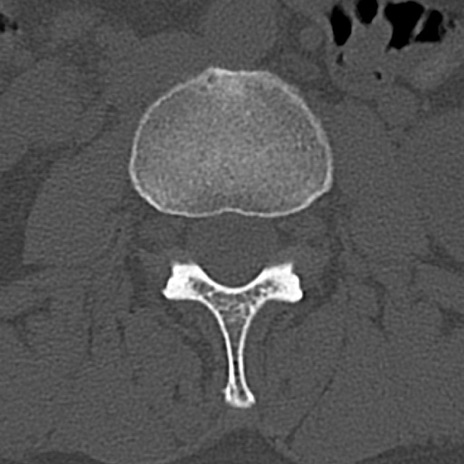

腰椎CT

横断像と矢状断像